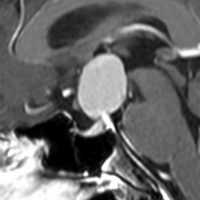

鞍隔膜下 infradiaphragmic type

7歳の子が視力障害で発症しました。両耳側半盲という症状です。典型的な鞍隔膜下頭蓋咽頭腫です。ガドリニウム造影剤を入れないMRIでみえる,黄色い矢印の先の白い高信号は抗利尿ホルモンです。ですから下垂体機能もまだ残っていて,尿崩症はありません。視力障害が戻らないことがあるのでなるべく早く,経鼻的な手術で摘出した方がいいものです,簡単 o(^-^)o